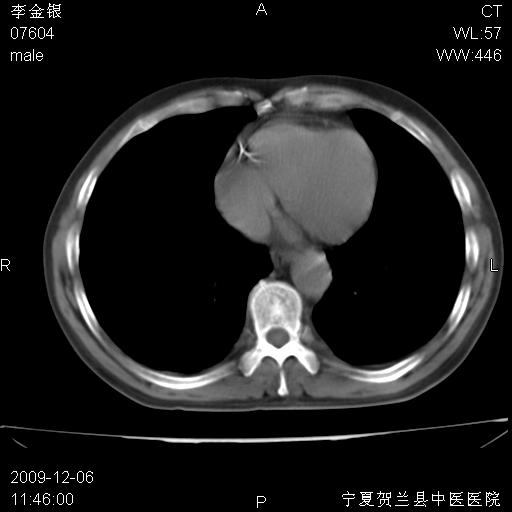

该病人 ,男,62岁,主因咳痰带血两天

考虑右肺中心型肺癌伴阻塞性肺炎及右肺门淋巴结转移,建议纤维支气管镜进一步检查。

考虑右侧中央型肺癌并阻塞性炎症及不张,建议ct增强!!

右肺中心型肺癌伴阻塞性肺炎及右肺门与纵膈淋巴结转移很典型,可纤维支气管镜进一步检查

右侧中央型肺癌伴纵隔内淋巴结转移考虑。

考虑右侧中央型肺癌伴右肺上叶后段阻塞性炎症、肺不张、右肺门和纵隔淋巴结肿大。

右肺上叶中心型肺癌,阻塞性肺炎、右肺门和纵隔淋巴结转移。